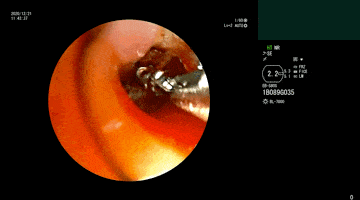

经纤支镜检查发现气管插管尖端有粘稠坏死物阻塞,普通活检钳难以抓取

活检钳钳取异物但其中部分异物与管壁相贴,操作难度极大,稍微不慎很